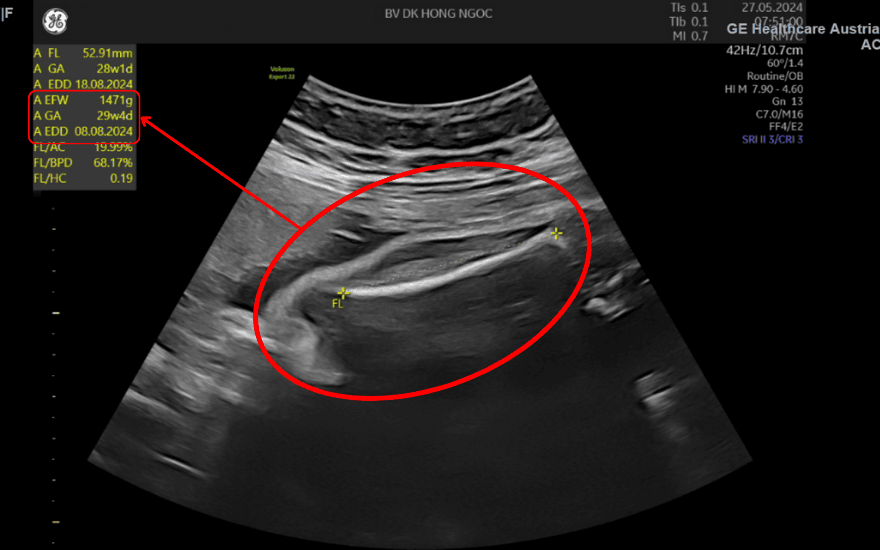

Thai phụ có nguy cơ dọa sảy khi thai mới ở mốc 29 tuần và cân nặng thai mới chỉ 1,4kg

Ths. BSCKII Đỗ Văn Tú (Trưởng khoa Sản Phụ khoa - BVĐK Hồng Ngọc Yên Ninh) cho biết: “Đây là 1 trường hợp vô cùng đặc biệt. Thứ nhất, thai phụ mang song thai, nguy cơ đẻ non rất cao. Thứ 2, thời điểm phát hiện nguy cơ sinh non ở tuần thứ 29 thì cả 2 thai còn rất nhỏ, siêu âm mỗi bé được 1,4kg. Vì vậy, việc điều trị giữ thai cho thai phụ chắc chắn sẽ gặp nhiều khó khăn”.